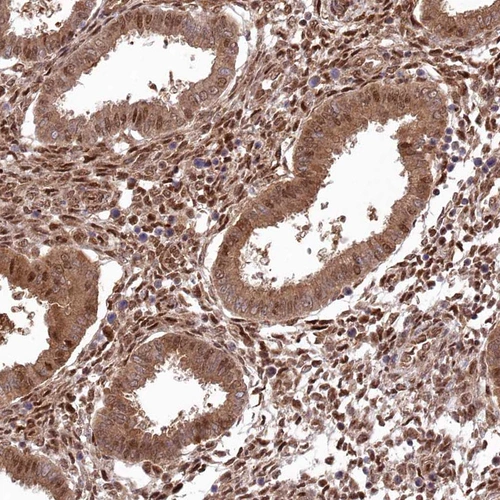

Immunohistochemical staining of human testis shows moderate to strong nuclear positivity in cells in seminiferous ducts.